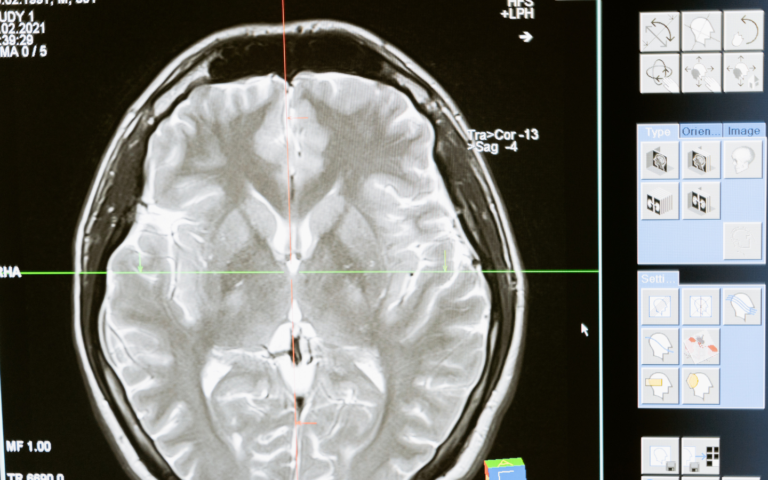

A diagnosis of a neurological disorder often comes with a heavy prognosis. For conditions like…

When a neurological disorder enters someone’s life, it often feels like the ground has shifted.…